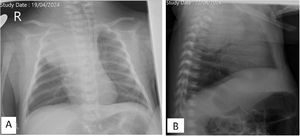

Ecografía torácica realizada con sonda lineal de alta frecuencia. A)Plano longitudinal a nivel de campo pulmonar anterior, superior derecho. Adecuado deslizamiento pleural, buena aireación en todos los campos pulmonares, con patrón de líneas A y puntuación de Brat de 0 puntos. B)Plano supraclavicular derecho. Consolidación sin broncograma aéreo ni captación en el doppler con borde profundo bien definido y redondeado de 6cm de diámetro máximo.